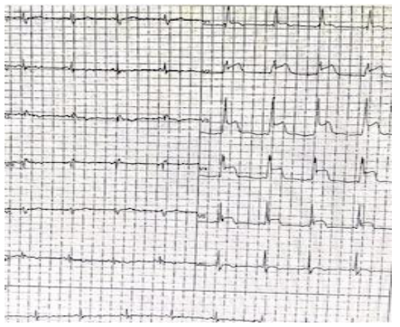

No mesmo dia você recebe um paciente de 70 anos, que relata dor torácica há 02 horas de forte intensidade, acompanhada de náuseas e sudorese. Paciente relata ser hipertenso, dislipidêmico e ex-tabagista. Ao exame: PA: 150x100mmHg e FC:72 bpm. Você também solicita ECG que veio conforme imagem abaixo:

Sua hipótese diagnóstica é: